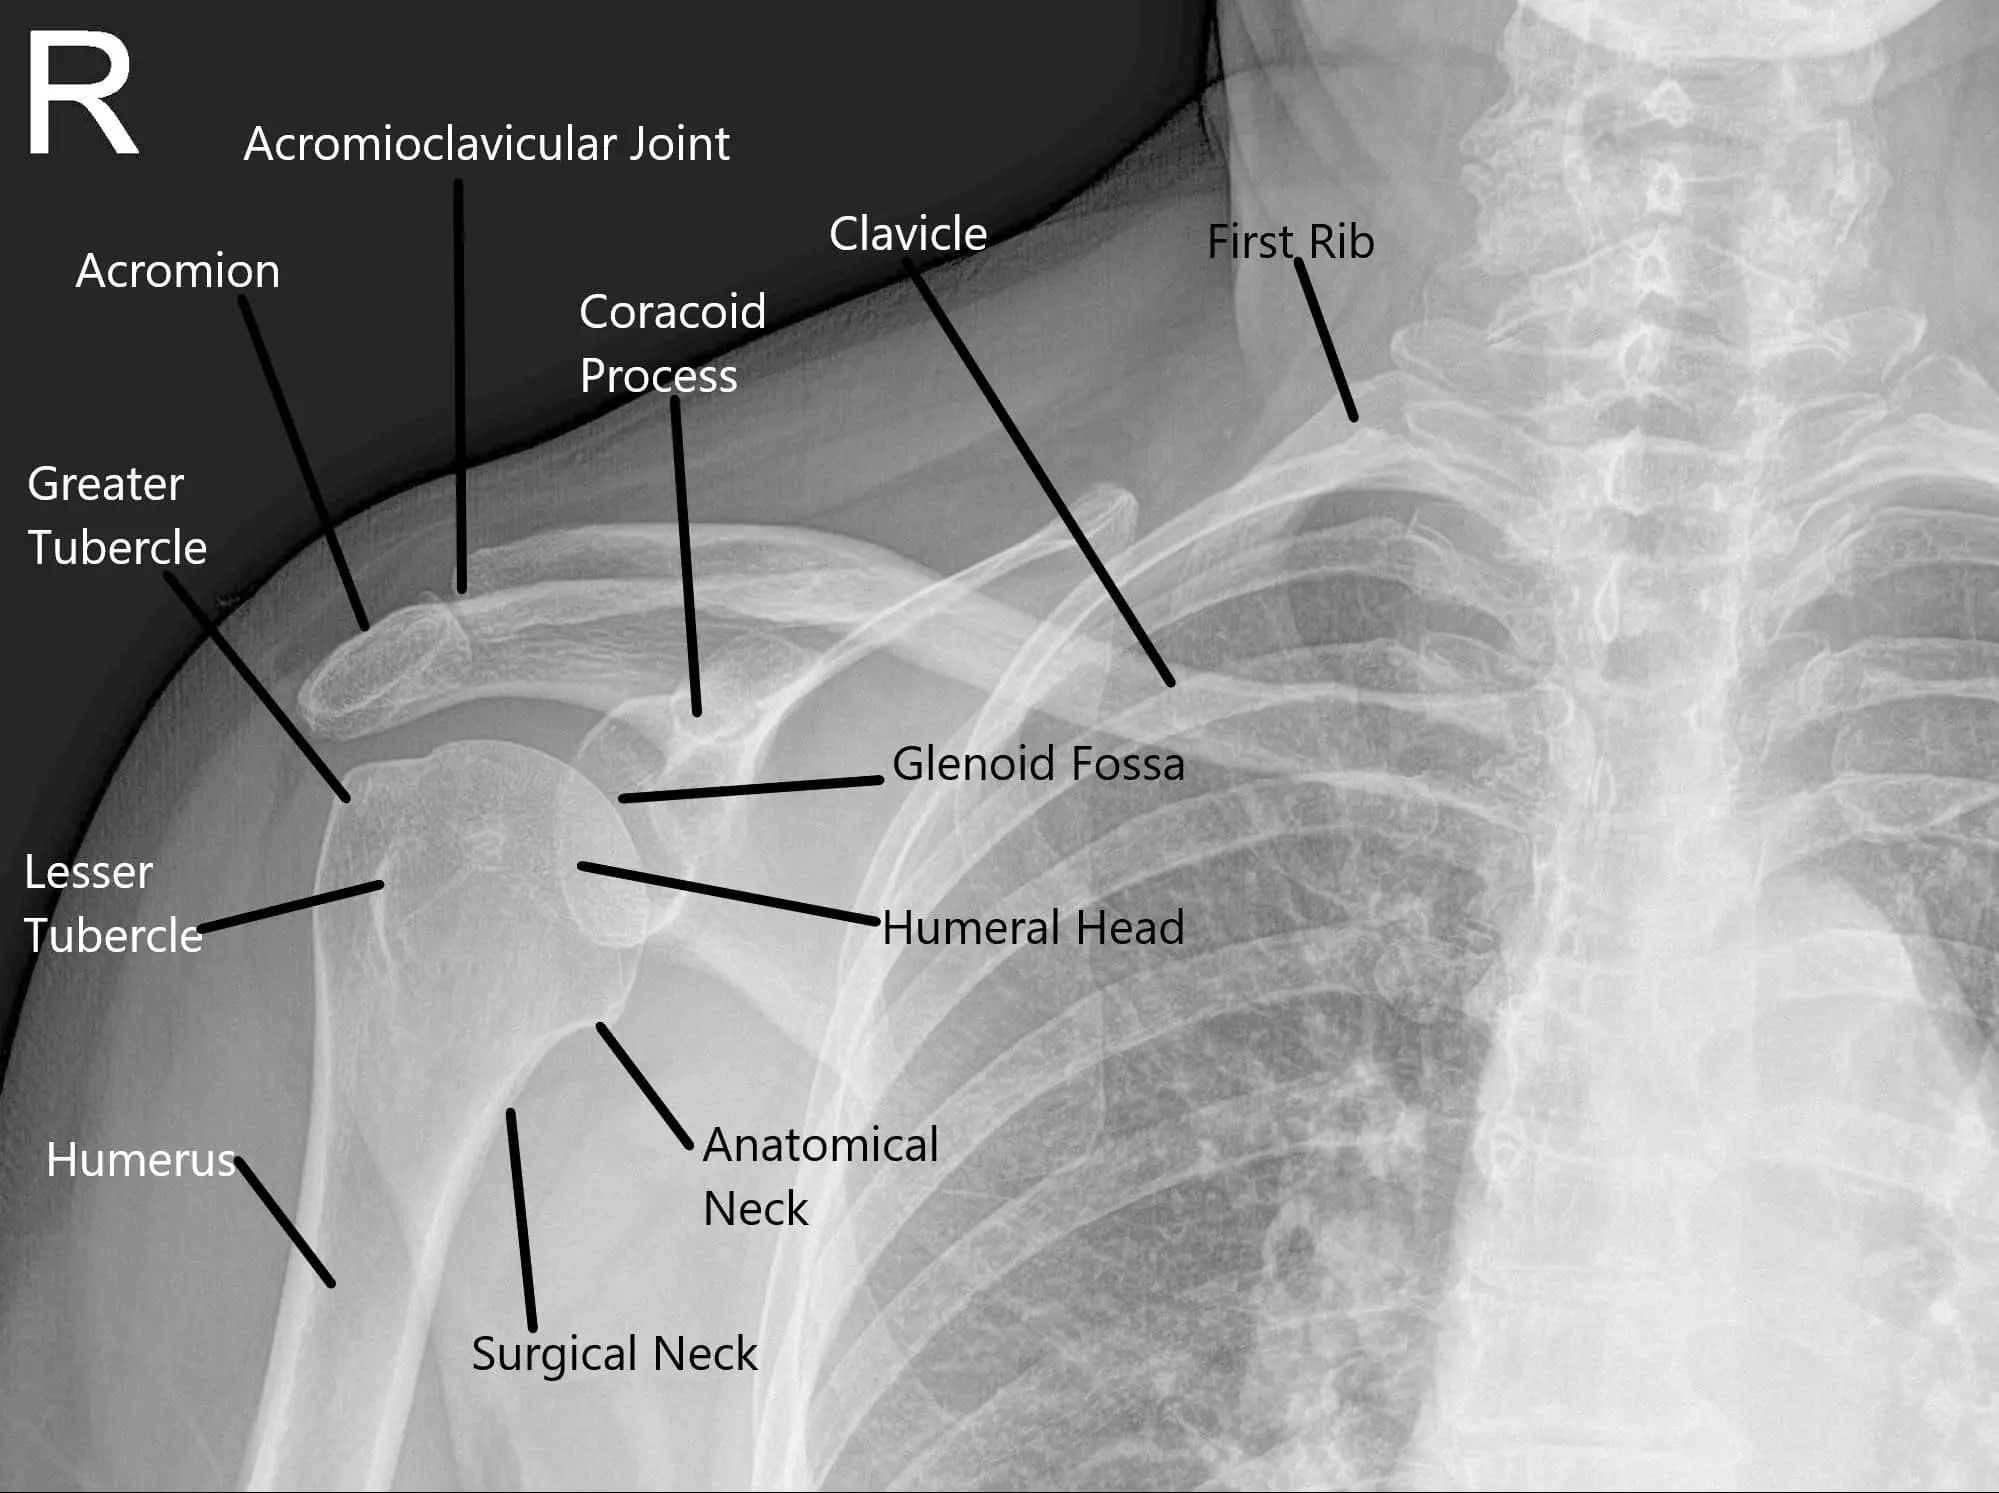

X-ray of the shoulder joint in the AP view.

The scapula is a triangular bone located on the back of the ribcage. It plays a crucial role in shoulder movement and stability. The scapula glides over the ribcage during arm movements, supported by various muscles and ligaments. The subscapularis and serratus anterior muscles help stabilize the scapula and enable smooth motion. The scapula also forms joints with the humerus (upper arm bone) and clavicle (collarbone), which are essential for arm mobility.

The diagnosis of snapping scapula syndrome is made based on a thorough physical examination and medical history. Physicians will often ask about the patient’s activity levels and any history of trauma or repetitive shoulder movements. Imaging techniques, such as X-rays, CT scans, and MRI, are used to evaluate bone structure, detect fractures, and assess soft tissues like muscles, tendons, and bursae. X-rays may reveal bone malformations, while CT scans and MRIs provide more detailed images of the shoulder structures.